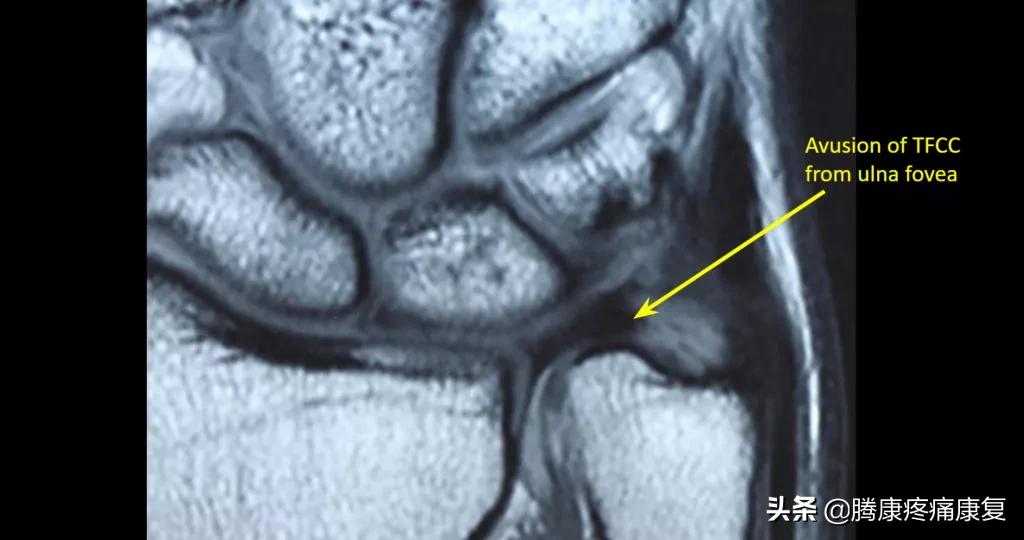

如果怀疑TFCC有损伤,通常会进行X光检查,以评估骨折、关节不稳和尺骨变化(前臂骨的长度)核磁共振成像有助于观察形成TFCC的软骨和韧带。